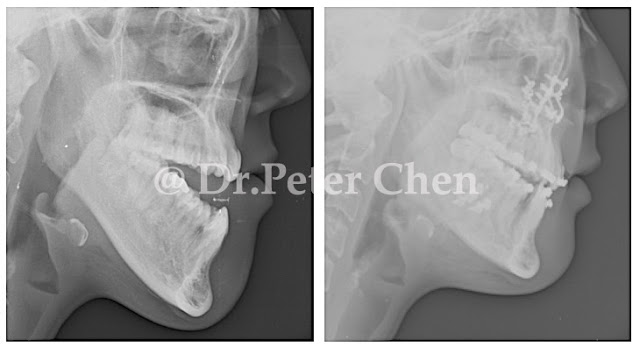

療程效果因人而異,上圖為該案例實際術後成效

傳統的正顎手術治療對於戽斗的情況 ( class III occlusion ),手術前需要花一年(有時更久)的時間,將內倒的下排牙齒向外翻,這樣的矯正方式,會使得戽斗在這一年中變得更為 嚴重

手術優先 ( Surgery-first ) 的治療方式,手術前不需矯正(少部分的患者只需要花一點時間將牙齒排齊),先用正顎手術將臉型及咬合調整到適當的位置,術後再用約一年的時間把牙齒矯正好,這樣一方面能讓病患省去術前難熬的一年時間,一方面也能夠將整個療程時間縮短,缺點是手術及矯正的技術可能都較傳統手術方式來得困難,對於醫師是種考驗。